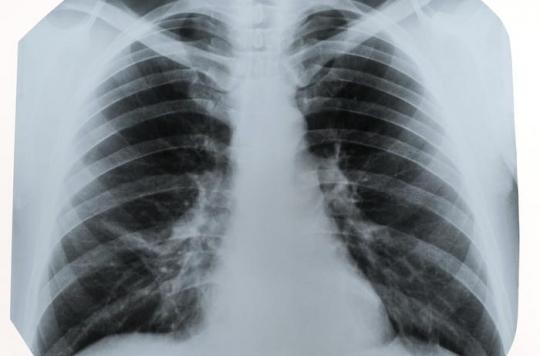

3 Vascularisation pulmonaire a) Chez le sujet normal Les 2 artères pulmonaires ont un calibre maximum de 15 mm;. Dump files to blosc to compress datasets and thus accelerate loading;. Elle présente des caractéristiques qui font qu’un diagnostic précis est important Dans le cas de la tuberculose pulmonaire, le traitement est long et spécifique, différent des traitements appliqués dans d’autres infections bactériennes.

One year after, a fibroscopy showed a necrosis of the right main bronchus mucosae and the CT showed a radioinduced aneurysm protruding into the right inferior lobular bronchus The patient eventually died a few hours later. Parenchyme pulmonaire •«Trame » = vaisseaux Ø vasculaire plus large aux bases / sommets Ø bases / sommets = 2 / 1 en position debout •Symétrie de transparence et volume des 2 hémithorax bronches visibles de façon très proximale visible 15 mm de la paroi Parenchyme pulmonaire. La radiographie pulmonaire permet aux médecins de visualiser les organes intrathoraciques comme les poumons, la trachée, les bronches, le médiastin et la plèvre (Double feuillet qui recouvre le poumon).

La tomodensitométrie thoracique est la TDM la plus réalisée en pratique courante L’objectif de cet article, est, par l’intermédiaire de nombreuses images, et d’explications, d’appréhender de manière simple l’anatomie pulmonaire, afin d’être précis dans la localisation d’une lésion pulmonaire dans le cadre d’un bilan diagnostique, d’un suivi, ou après pneumonectomie. (Slideset Comment examiner une radio du thorax ?) slide 10 Les infiltrats bilatéraux d'apparence pelucheuse sont caractéristiques d'un oedème pulmonaire significatif Ce cliché d'une radiographie thoracique AP en supination provient d'un sujet afébrile présentant une détresse respiratoire grave ;. La séquestration pulmonaire est une malformation congénitale caractérisée par la vascularisation artérielle d'origine systémique d'un segment du poumon Nous décrivons une observation de séquestration pulmonaire traitée par ligature de l'artère anormale sans résection pulmonaire associée.